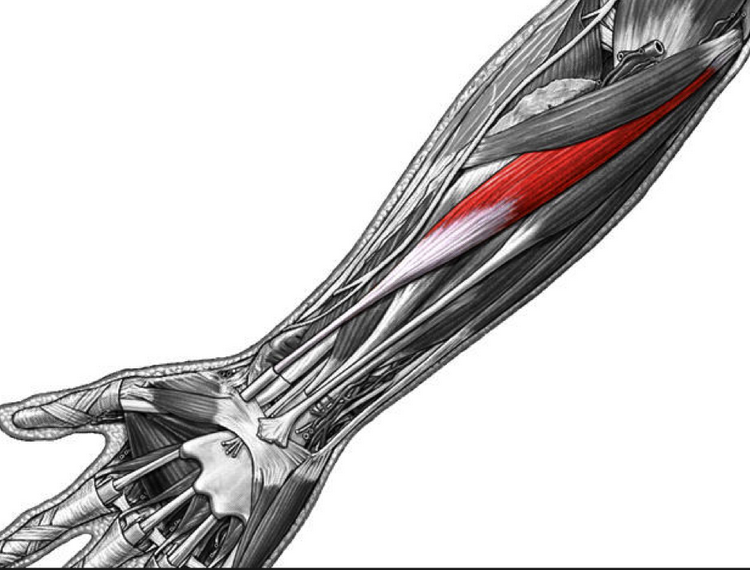

Анатомия мышцы Palmaris Longus